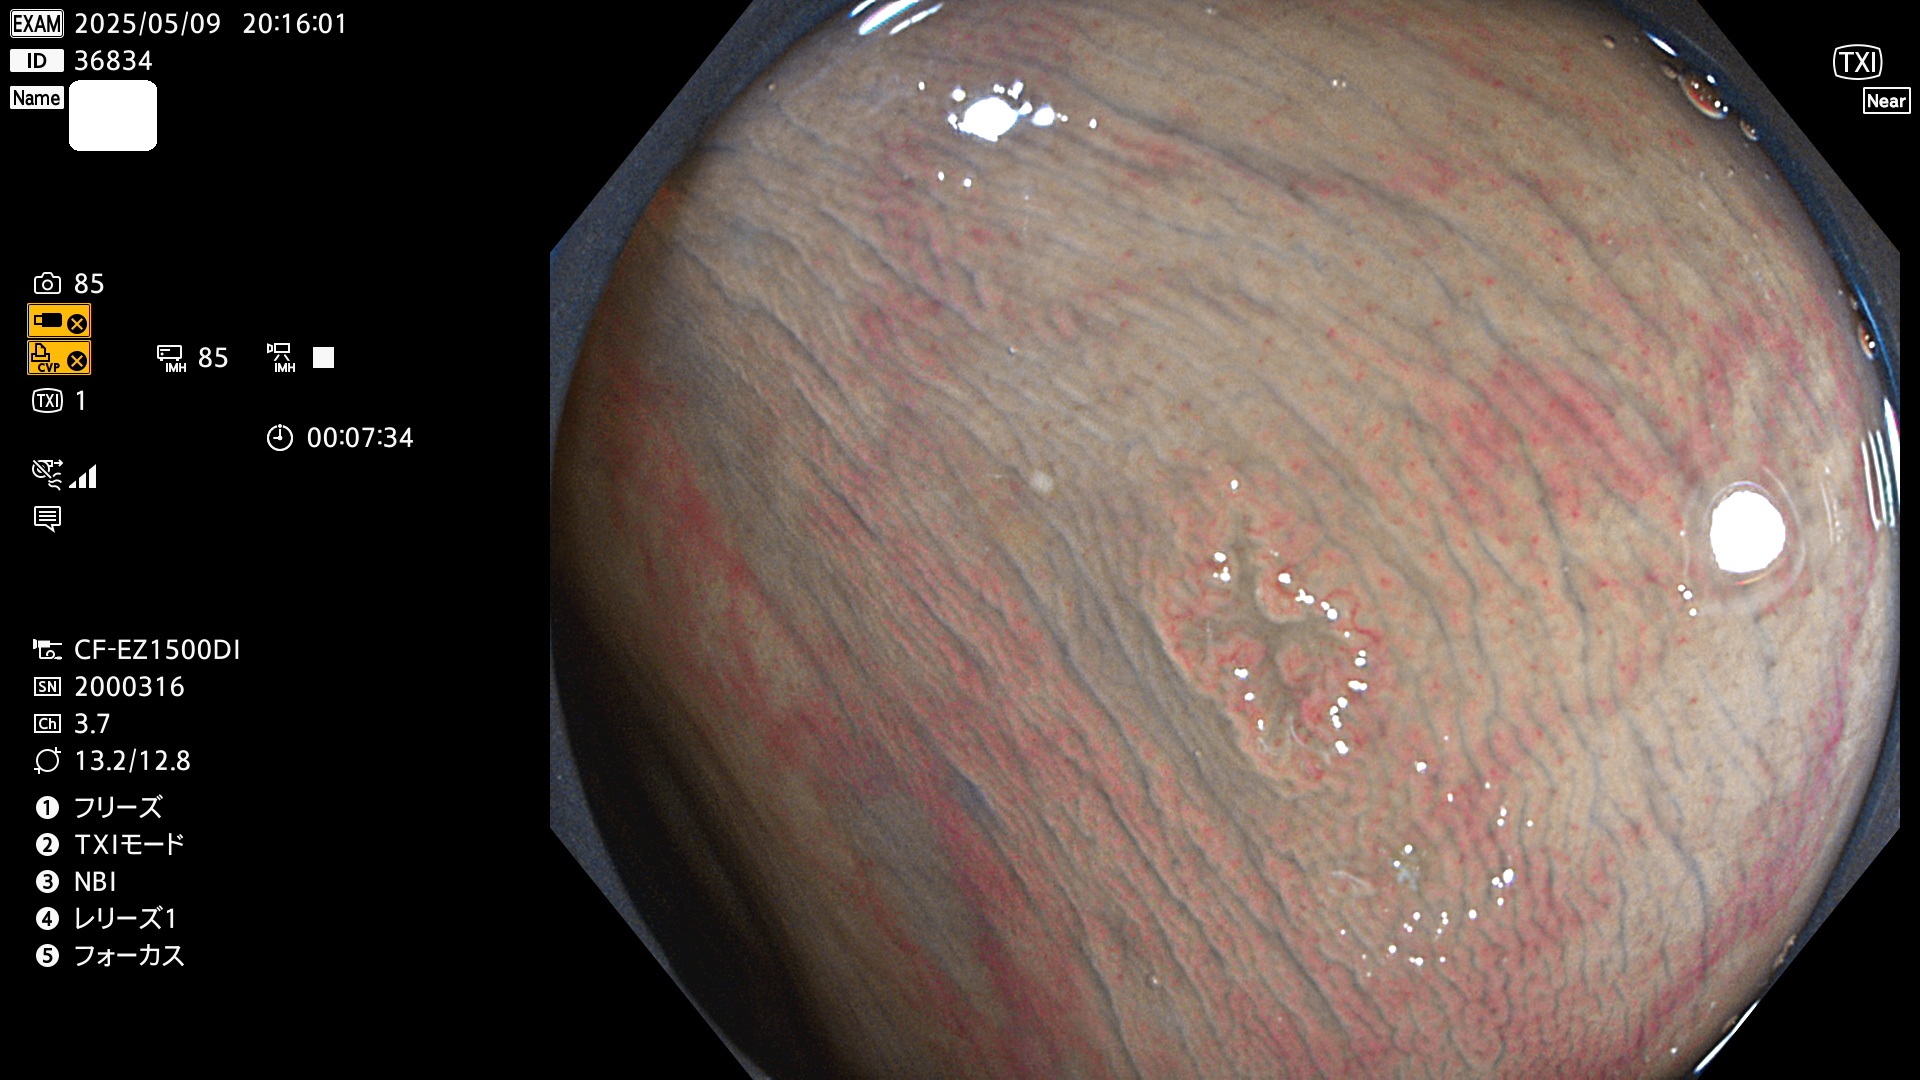

完全に平坦な物をUb、陥凹している物をUcと呼びます。Ubは認識が困難で、Ucはびらん(炎症)と紛らわしいために見落とされやすく、「内視鏡後・大腸癌」の原因になります。

抽出の対象期間 2025年5月8日〜5月11日の4日間(48件の検査)14個 (14/48=29%)